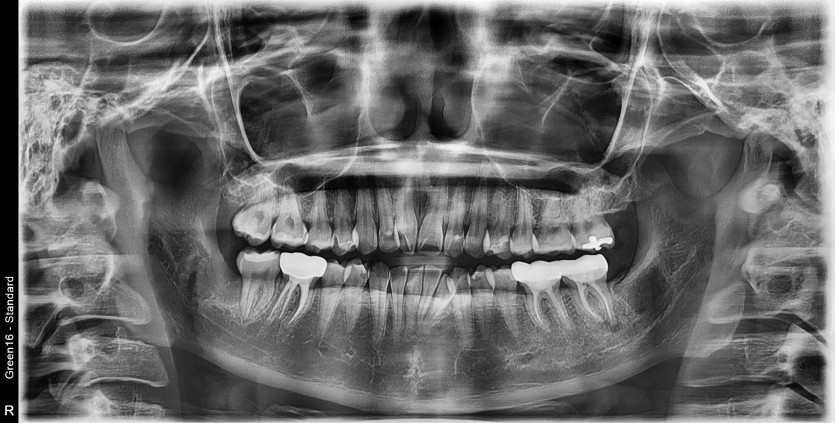

#48 사랑니 발치

구강 외과 전문의가 당일 발치했습니다.